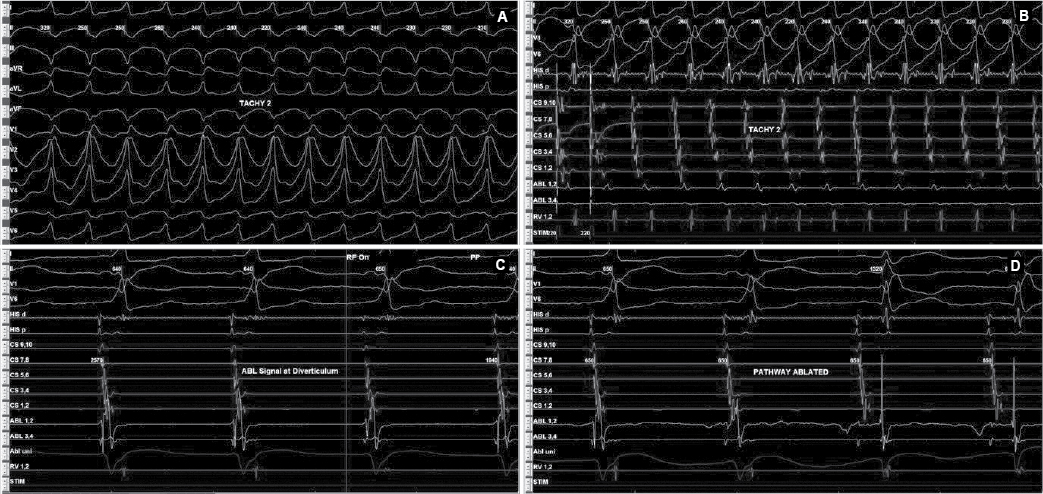

Later on, during programmed atrial stimulation with burst pacing, patient developed another broad complex tachycardia (TCL = 220 ms) with 1:1 AV relationship. The tachycardia was hemodynamically unstable and led to ventricular fibrillation and required direct current cardioversion (DCCV) with 200J (Fig. 4). With the help of steerable ablation catheter, earliest atrial activation during ventricular pacing and earliest ventricular signal in sinus rhythm was mapped at the septal tricuspid annulus (RA mapping) and septal mitral annulus (LA mapping). Afterwards coronary sinus angiogram was taken, which showed a coronary sinus diverticulum near the decapolar coronary sinus 5-6 electrodes (Fig. 5). Radiofrequency applications were delivered at the neck of diverticulum that leads to disappearance of pre-excitation (Fig. 6). Afterwards aggressive programmed stimulation done on and off with isoproterenol that did not induce any atrial arrhythmias.

Figure 4. Antidromic tachycardia (A and B) involving posteroseptal pathway. EGMs recorded (C) inside diverticulum neck that was ablated successfully (D).